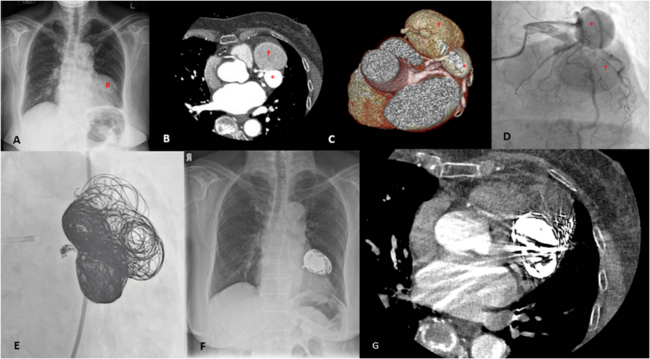

A 73-year-old female presented with exertional dyspnea and was found to have a coronary artery to pulmonary artery (PA) fistula with 2 sequential giant aneurysms. Her chest radiograph (Figure, A) showed a mass (#) above the cardiac silhouette. Computed tomography (CT) coronary angiogram (Figure, B) with 3-dimensional reconstruction (Figure, C) identified a coronary artery to PA fistula arising from a septal branch of the left anterior descending artery (LAD) draining into the main pulmonary trunk. The fistula was large with 2 sequential giant aneurysms (* and †) before draining into the PA. A coronary angiogram (Figure, D; Video 1) confirmed the presence of the fistula with the 2 giant aneurysms and no significant coronary artery stenoses.

Due to persistent symptoms and being deemed a poor surgical candidate by the heart team, transcatheter closure was planned with a strategy using endovascular coils to embolize both the feeder from the proximal LAD and the outlet at the PA. The left coronary artery was engaged with a 6-French XB 3.5 guide catheter, and the septal feeder artery was first wired with a 0.014-inch guidewire and microcatheter support. The proximal aneurysm, followed by the distal aneurysm, were then wired. Wiring of the fistula outflow to the PA via the antegrade approach was not successful, and thus a retrograde transvenous approach through the pulmonary artery was attempted; this was also unsuccessful. Coil embolization of the 2 giant aneurysms was then performed using 34 Medtronic Concerto Helix coils (sixteen 20 x 50-mm, seven 18 x 40-mm, seven 16 x 40-mm, and four 14 x 30-mm coils). The septal artery feeder was coiled with 5 Medtronic Concerto coils (one 8 x 30-mm, one 6 x 20-mm, two 4 x 8-mm, and one 3 x 8-mm coils) (Figure, E, F; Video 2). At 6-month follow-up, the patient reported improvement in her breathlessness and a repeat CT coronary angiogram (Figure, G) showed reduction in the size of the aneurysm with no evidence of flow across the fistula.